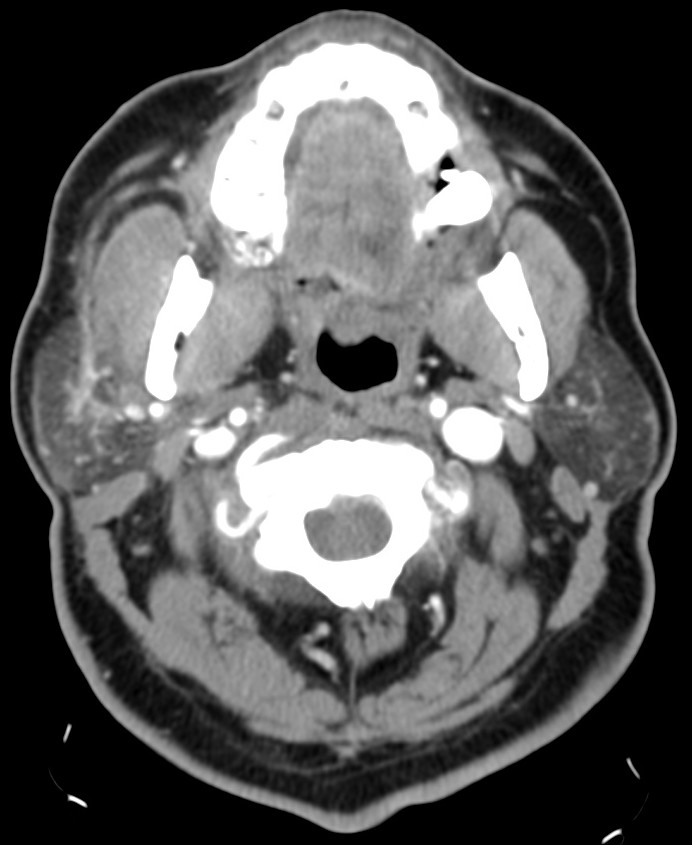

Amigdalitis, Absceso periamigdalino y parafaríngeo:

La clínica no permite diferenciar con exactitud entre celulitis y absceso y no permite determinar con exactitud la extensión del proceso. Clínicamente se sospecha un absceso cuando existe dolor en región cervical y amígdalas que empeora progresivamente a pesar de antibióticoterapia oral, fiebre persistente, odinofagia, voz gangosa, adenopatías cervicales dolorosas y en algunas ocasiones trismus.

Hallazgos:

- Aumento de tamaño de las amigdalas (amigdalas «besándose») con aumento de realce tras tras aplicación de contraste iv.

- En fases avanzadas surgen hipodensidades parenquimatosas o colecciones líquidas debido al edema y la celulitis existente.

- Un absceso periamigalino se diferencia de la celulitis porque presenta una licuefacción/colección central con anillo periférico realzado que puede o no presentar burbujas de aire en su interior. Un absceso de morfología irregular indica estadio más evolucionado.

- El absceso puede extenderse al espacio parafaringeo, constituye el 9% de todas las masas parafaríngeas.

- La distinción entre celulitis y absceso es importante en lo que al tratamiento se refiere. Si existe una colección drenable, la aspiración es el tratamiento requerido. Una colección con anillo periférico realzado, es compatible con absceso drenable en el 63-77% de los casos, población pediátrica y adulta incluida.

- Puede observarse agrandamiento y realce de la úvula.

- Es frecuente identificar adenopatías cervicales.

- Es frecuente observar una mala delimitación de los tejidos blandos adyacentes y las adenopatías cervicales.